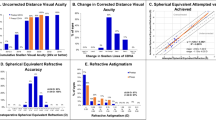

Uncorrected visual acuity

Preoperative and postoperative monocular uncorrected visual acuity (UVA) logMAR are shown in Fig. 3. The largest improvements in visual acuity overall were for monocular uncorrected near visual acuity (UNVA) measured at 40 cm. Mean monocular UNVA for all patients was significantly improved at all follow-up visits and was 0.25 ± 0.18 logMAR (~20/35 snellen) at 24 months postoperatively compared to preoperative monocular UNVA of 0.36 ± 0.20 logMAR (~20/45 snellen) (p = 0.000050). Binocular UNVA improved from +0.20 ± 0.16 logMAR (~20/32 snellen) preoperatively, to +0.12 ± 0.14 logMAR (~20/25 snellen) at 24 months postoperatively (p = 0.0014).

Monocular uncorrected intermediate visual acuity (UIVA) measured at 60 cm increased postoperatively for all time points compared to preoperative UIVA, and was statistically significant at 3 months postoperatively (p = 0.0040). At 24 months postoperatively, there was no statistically significant loss or change from preoperative refraction. Similar to UIVA, monocular uncorrected distance visual acuity (UDVA) measured at 4 m increased at all time points and was statistically significant at 3 and 6 months postoperatively (p = 0.0080 and p = 0036). Binocular UIVA increased for all points compared to preoperative UIVA and was statistically significant at 3 months postoperatively (p = 0.0047). At 24 months postoperatively, binocular UDVA showed no statistically significant loss or change from preoperative refraction.

Distance corrected visual acuity

Preoperative and postoperative monocular distance corrected visual acuity (DCVA) in logMAR are shown in Fig. 3. Similar to UVA, the largest improvements in visual acuity were for distance corrected near visual acuity (DCNVA) measured at 40 cm. Mean monocular DCNVA for all patients was significantly improved (p = 0.000000019) at all follow-up visits and was 0.21 ± 0.18 logMAR (~20/32 snellen) at 24 months postoperatively compared to preoperative monocular DCNVA of 0.34 ± 0.18 logMAR (~20/45 snellen). Binocular DCNVA improved from +0.21 ± 0.17 logMAR (~20/32 snellen) preoperatively, to +0.11 ± 0.12 logMAR (~20/25 snellen) at 24 months (p = 0.00026).

Monocular distance corrected intermediate visual acuity (DCIVA) measured at 60 cm increased postoperatively for all time points compared to preoperative DCIVA, and was statistically significant at 1, 3, 6, and 12 months postoperatively (p = 0.0019, p = 0.00065, p = 0.000031, and p = 0.0087). At 24 months postoperatively there was no statistically significant loss or change from preoperative refraction. Similar to DCIVA, monocular corrected distance visual acuity CDVA measured at 4 m increased at all time points and was statistically significant at 3 months postoperatively (p = 0.015). Binocular DCIVA increased for all points compared to preoperative DCIVA and was statistically significant at 1, 3, 6, and 12 months postoperatively (p < 0.0087). At 24 months postoperatively, binocular CDVA showed no statistically significant loss or change from preoperative refraction.

Stability, intraocular pressure, and stereopsis

The spherical equivalent refraction, shown in Fig. 4, was stable over 24 months operatively. At 18 months postoperatively, the spherical equivalent refraction was significantly improved at 0.00 ± 0.46 D compared to preoperative refraction 0.16 ± 0.42 D (p = 0.0015).

Intraocular pressure (IOP) as measured by pneumatic tonometry is shown in Fig. 5. Patient IOP averaged of 13.56 ± 3.23 mmHg preoperatively. Patient IOP was significantly lower than preoperative IOP at all time points apart from 1 month postoperatively (p < 0.027). The average IOP at 24 months postoperatively was 11.74 ± 2.64 mmHg and was significantly improved from preoperative IOP (p = 0.000063).

Stereopsis testing, as measured by Randot stereoscopic tests, is shown in Fig. 6. Remarkably, stereoacuity improved after the LaserACE procedure. This was statistically significant at 18 months postoperatively (49.1 ± 16.9 s of arc; p = 0.012). Preoperatively, mean stereoacuity was 75.8 ± 29.3 s of arc, which improved to 58.6 ± 22.9 s of arc at 24 months, but was not statistically significant.